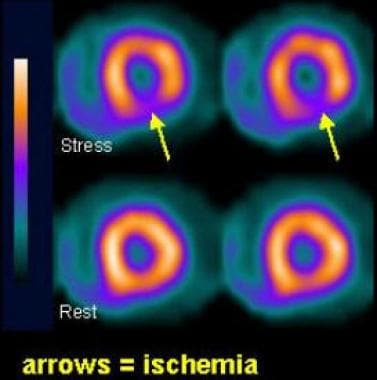

Myocardial Perfusion SPECT: Background, Indications, Contraindications Interpretation of SPECT/ CT Myocardial Perfusion Images: Common Arti- facts and Quality Control Techniques1 Heart attack, SPECT scan - Stock Image - C013/1043 - Science Photo Library Spect Scan Heart